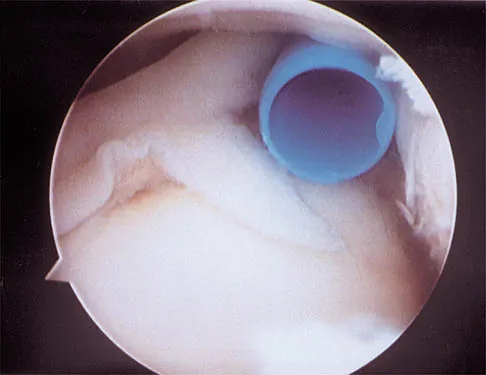

A football player sustains a traumatic anterior inferior dislocation of the shoulder in the last game of the season. It is reduced 20 minutes later in the locker room. The patient is neurologically intact and has regained motion. If the patient undergoes arthroscopic evaluation, what finding is seen most consistently?

Explanation